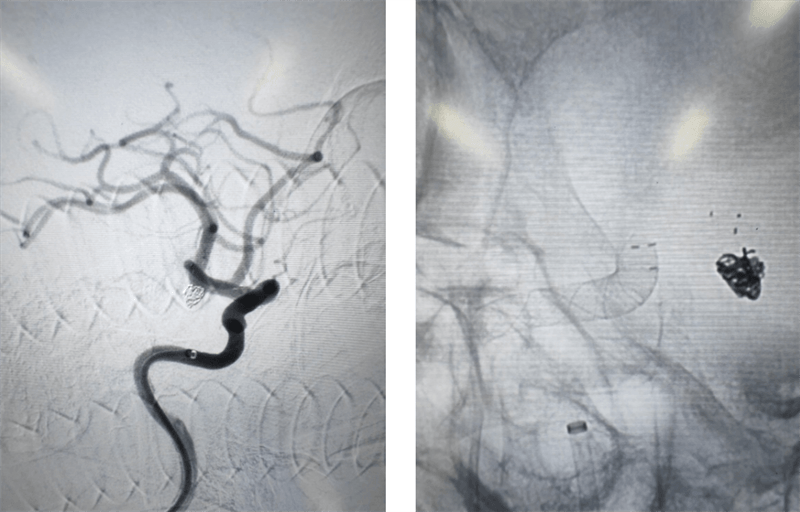

術(shù)中,介入團隊對患者右側(cè)頸內(nèi)動脈末端兩枚動脈瘤采用密網(wǎng)支架覆蓋,左側(cè)脈內(nèi)動脈末端動脈瘤采用彈簧圈填塞。在手術(shù)過程中,對患者左側(cè)頸內(nèi)動脈使用6F長鞘,6F中間導(dǎo)管建立通路 ,分別使用X17 與headway-17微導(dǎo)管輸送Atlas輔助支架和數(shù)枚彈簧圈完成填塞。右側(cè)頸內(nèi)動脈使用導(dǎo)引導(dǎo)管 GC-088-09 顱內(nèi)支撐導(dǎo)管同軸,在導(dǎo)絲引導(dǎo)下,將遠端通路導(dǎo)管DA6115ST至右側(cè)頸內(nèi)動脈海綿竇段。選擇合適工作角度,沿神經(jīng)血管導(dǎo)絲TNGW-14-200-S將TJMC18 Plus微導(dǎo)管送至大腦中動脈,沿TJMC18 Plus送入NUVA 4.5*25mm血流導(dǎo)向密網(wǎng)支架, 支架順利打開。支架釋放后造影可見支架顯影清晰,形態(tài)良好,無貼壁不良。支架釋放后觀察10分鐘,無異常。經(jīng)過幾個小時的奮戰(zhàn),手術(shù)終于順利結(jié)束,患者重獲健康。

術(shù)后影像